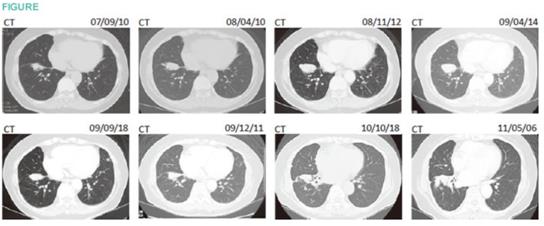

68岁女性,诊断时胸膜播种、对策纵隔淋巴结转移,cT4N3M0、Stage IIIb期肺癌。经小半年CBDCA+PTX联合化疗治疗后停止化疗,1次αβT细胞治疗后仍然进展,改用γδT细胞多次治疗后维持了3年以上。

中途CEA升高,仅用了2次单药化疗。